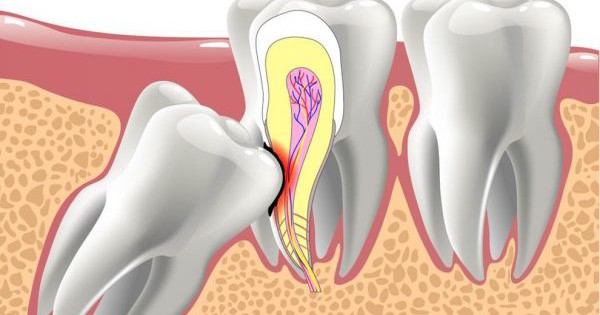

Hệ răng sữa và răng vĩnh viễn bắt đầu hình thành từ tuần thứ 6 của thời kỳ bào thai. Từ một loại tế bào được biệt hóa, qua nhiều giai đoạn phát triển và di chuyển về phía xương hàm để hình thành các mầm răng nằm trong xương hàm.

Trong quá trình hình thành mầm răng và di chuyển, có nhiều yếu tố tác động khiến các mầm răng không ở vị trí đúng mà nằm ở những chỗ khác. Ở vị trí lạc này, mầm răng vẫn phát triển thành răng hoàn chỉnh và được gọi là răng lạc chỗ. Có thể có từ một đến nhiều răng lạc chỗ.

Đặc điểm của răng mọc lạc chỗ

Răng lạc chỗ có những đặc điểm như sau:

- Thực chất răng lạc chỗ là răng được phát triển hoàn chỉnh nên sẽ giống răng thật.

- Gặp nhiều răng lạc chỗ là răng vĩnh viễn hơn là răng sữa.

- Răng có thể lộ ra ở trong miệng khiến bạn phát hiện ra hay bạn không hề biết có răng lạc chỗ, chỉ khi tình cờ đi khám, nha sĩ phát hiện ra có răng lạc chỗ. Ở trẻ em, bố mẹ thấy mãi răng con chưa thay hoặc răng sữa rụng rồi nhưng không thấy răng mới mọc lên.

- Răng có thể mọc ra hoặc không.